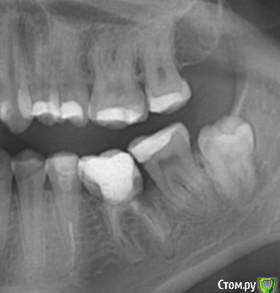

MariaF Опубликовано 12 февраля, 2016 Поделиться Опубликовано 12 февраля, 2016 Уважаемые доктора, Посоветуйте, можно ли спасти зуб? Идет разрушение, советуют удалять и ставить имплант. 1 1 Ссылка на комментарий

___49___ Опубликовано 12 февраля, 2016 Поделиться Опубликовано 12 февраля, 2016 (изменено) 6ку удалил бы. и чем раньше тем лучше т.к. между 6кой и 7кой идет резорбция(растворение) костной ткани (челюсти) из-за плачевного состояния корня 6ки (лечение которого считаю не целесообразным). Дальнейшее затягивание с удалением будет негативно сказываться на 7ке. Удаляйте, не тяните. Изменено 12 февраля, 2016 пользователем ___49___ Ссылка на комментарий

Doctor Vlad Опубликовано 15 февраля, 2016 Поделиться Опубликовано 15 февраля, 2016 в добавок ко всему яб восьмерку удалил еще! Ссылка на комментарий

Doctor Vlad Опубликовано 15 февраля, 2016 Поделиться Опубликовано 15 февраля, 2016 судя по снимку кость рассасывается за корнем 38 зуба! это не норма уже. Ссылка на комментарий

Doctor Vlad Опубликовано 15 февраля, 2016 Поделиться Опубликовано 15 февраля, 2016 на пародонтальную кисту похоже. она расти может... Ссылка на комментарий

Doctor Vlad Опубликовано 16 февраля, 2016 Поделиться Опубликовано 16 февраля, 2016 в идеале такого быть не должно! сравните со здоровыми зубами верхней челюсти. рассасывается - исчезает да Ссылка на комментарий